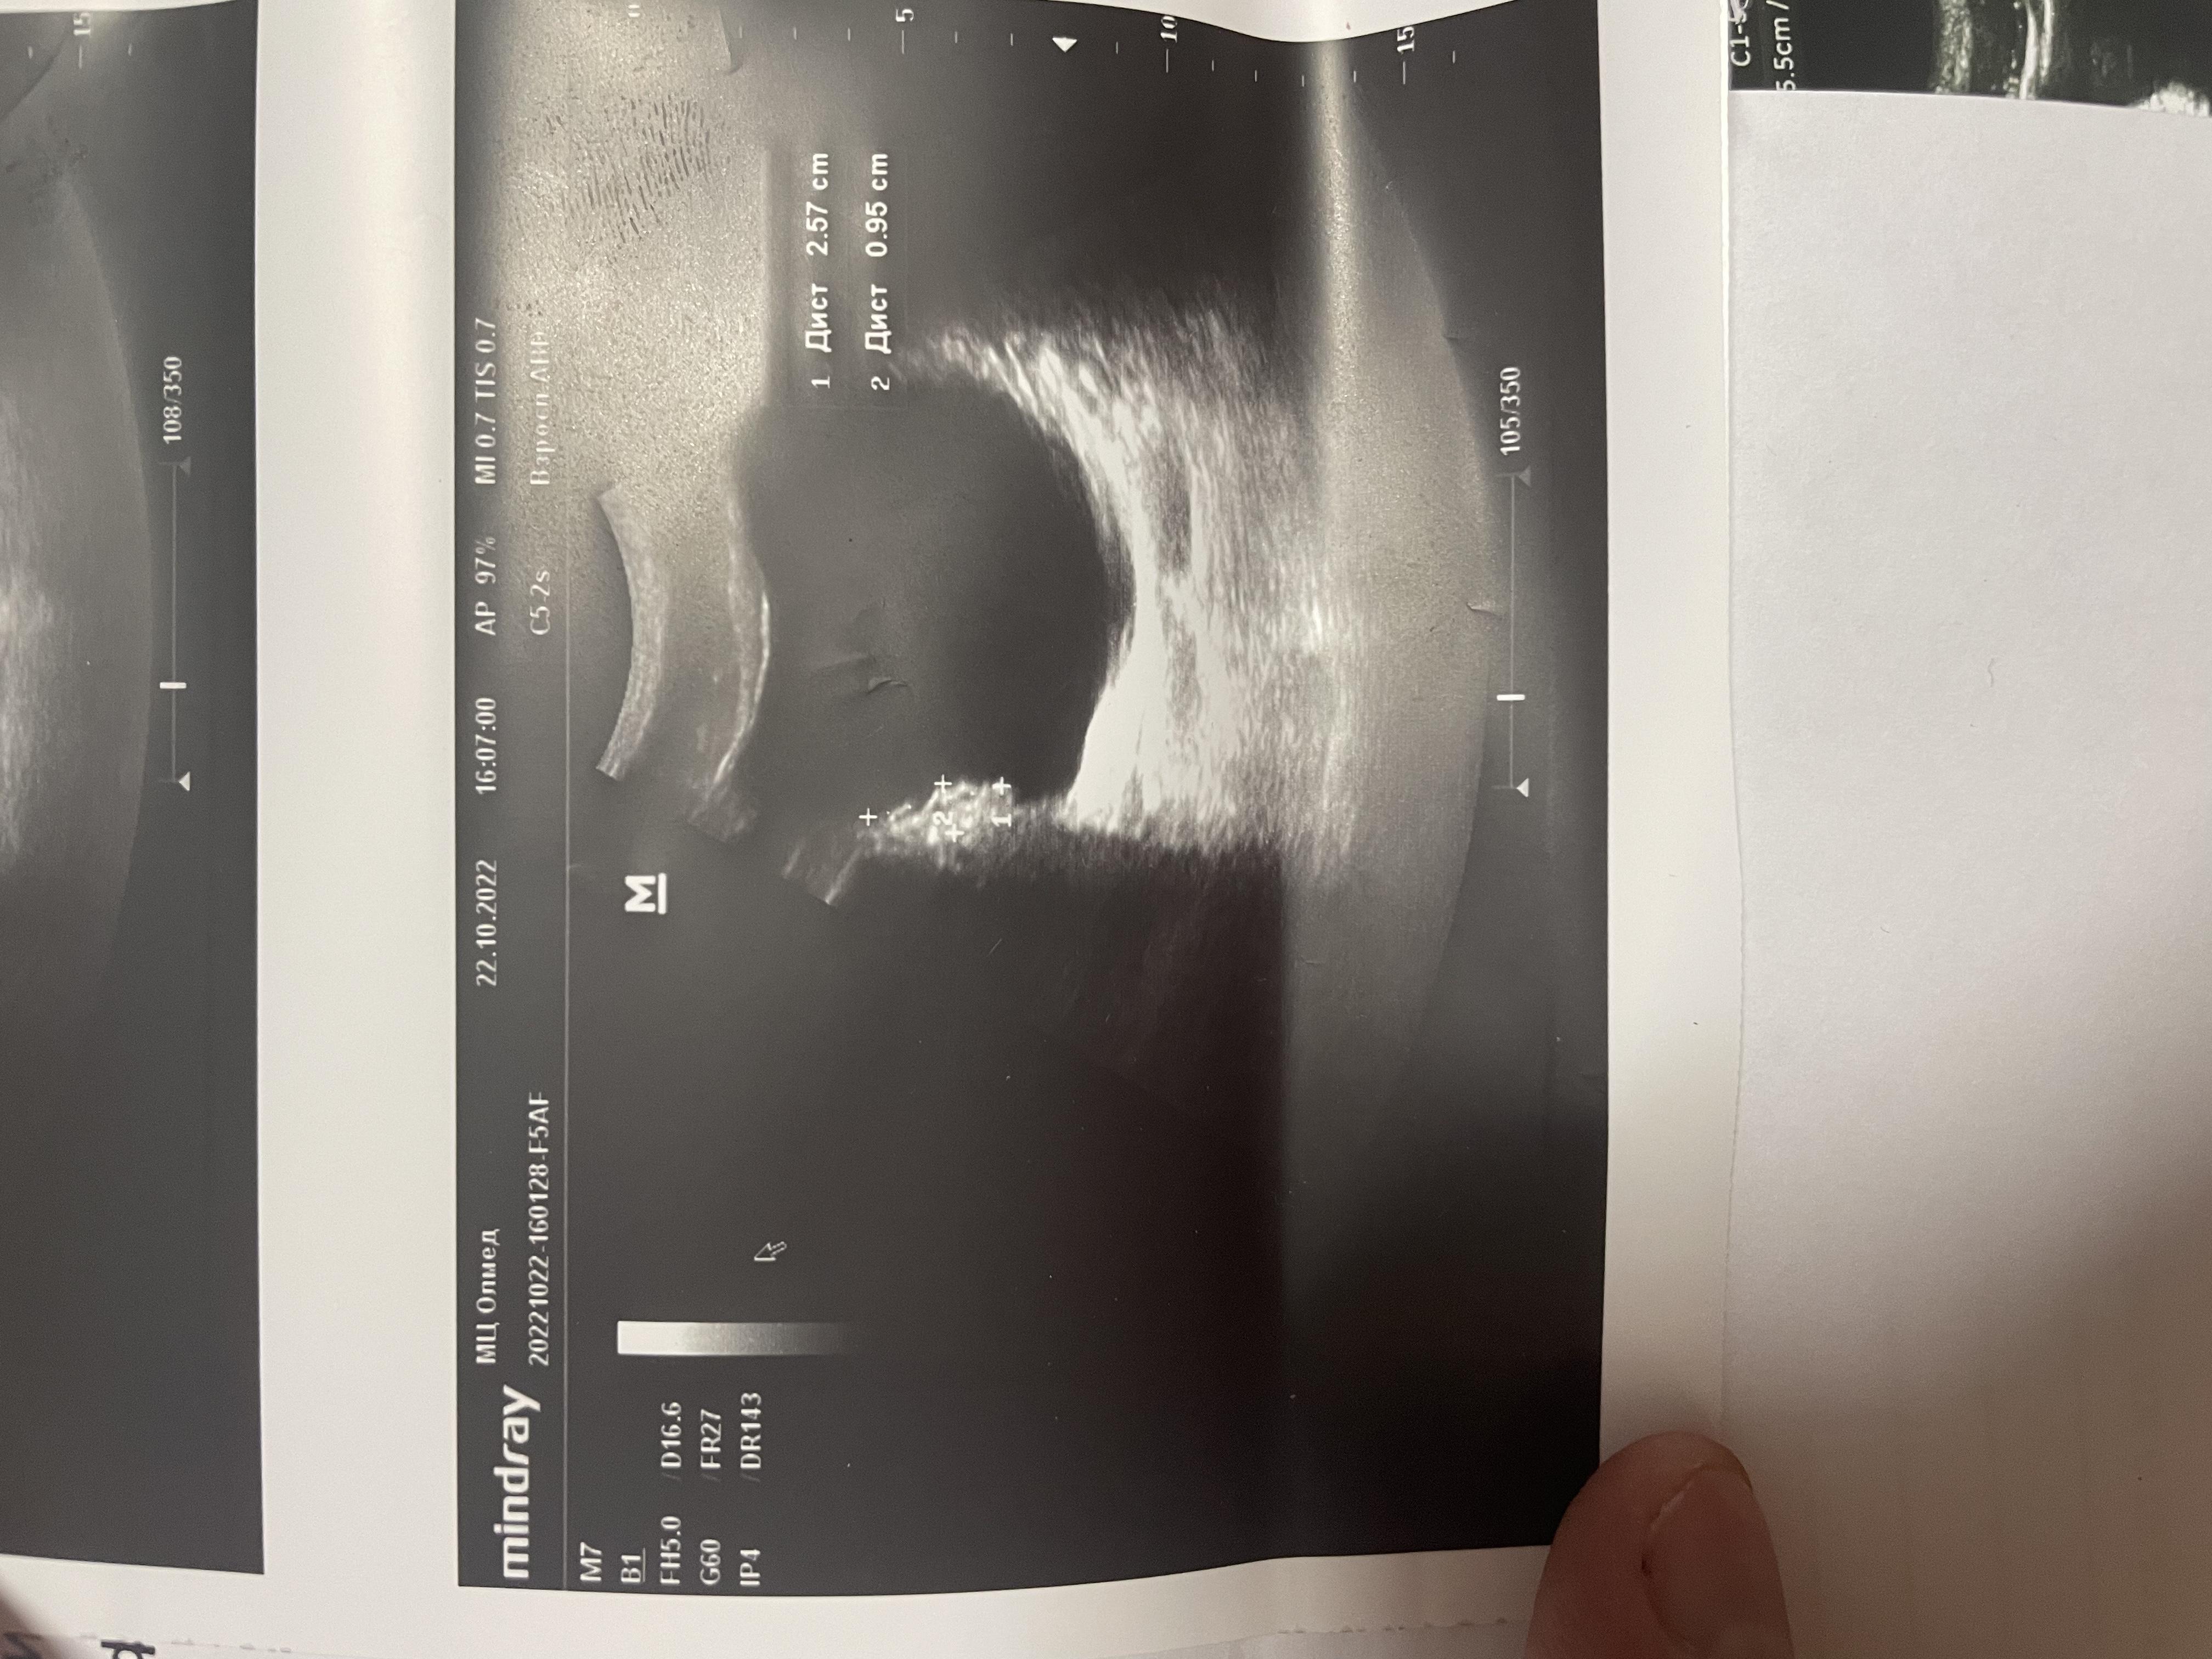

Здравствуйте, болят яички 1.5 года. 6 месяцев режет при мочеиспускании, боли в копчике (начинается с копчика, в течение дня усиливаются, поднимаются выше боли). Может ли это быть из-за мочевого пузыря? Фото прикрепил, там есть образование некое. Бак посев мочи отриц, эр, лейк. в норме, зппп отриц, в секрете простаты клебсиела, кровь в норме, млча в норма. Мрт поясницы делал, невролог сказал, что боли точно не из-за невролгии.

Добрый день! Вам нужно выполнить МРТ малого таза - там будет видно образование в стенке мочевого пузыря (если оно действительно есть). После этого надо обратиться к онкоурологу для интерпретации результатов МРТ и решения вопроса о дальнейшей тактике. Удачи.